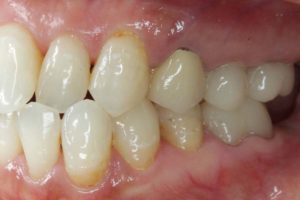

最後に、術前・術後のお写真をご紹介します。

院長のコメント 1年間お疲れさまでした。たくさん治療しましたが、「あっけなくおわりました。」とおっしゃって頂きありがとうございました。当院ではお一人1時間でお約束をお取りしていますので、20分や30分で細かく分けて治療するのに比べ、無駄がなく効率よく進みます。 さらに、治療用の椅子は1台(メインテナンス用の椅子がもう1台)しか置いていませんので、私はお一人の治療に1時間集中できますから、なおさら治療は進みます。 ただ、決して急いでいる訳ではなく、じっくり治療をしているのですが、一つ一つ確実にステップを踏むとミスが少なくなり、その結果治療も早く進んでいくのです。 さて、この患者さんは、ブリッジをやり直す時にそのままブリッジにするかインプラントにするかとても迷われていたのですが、最終的にはインプラントを選択されました。アンケートにもありますように、皆さんが考えている程インプラント治療は痛みを伴うものではありません。今回のケースでも、全く痛みはなく痛み止めを飲むこともなかったそうです。